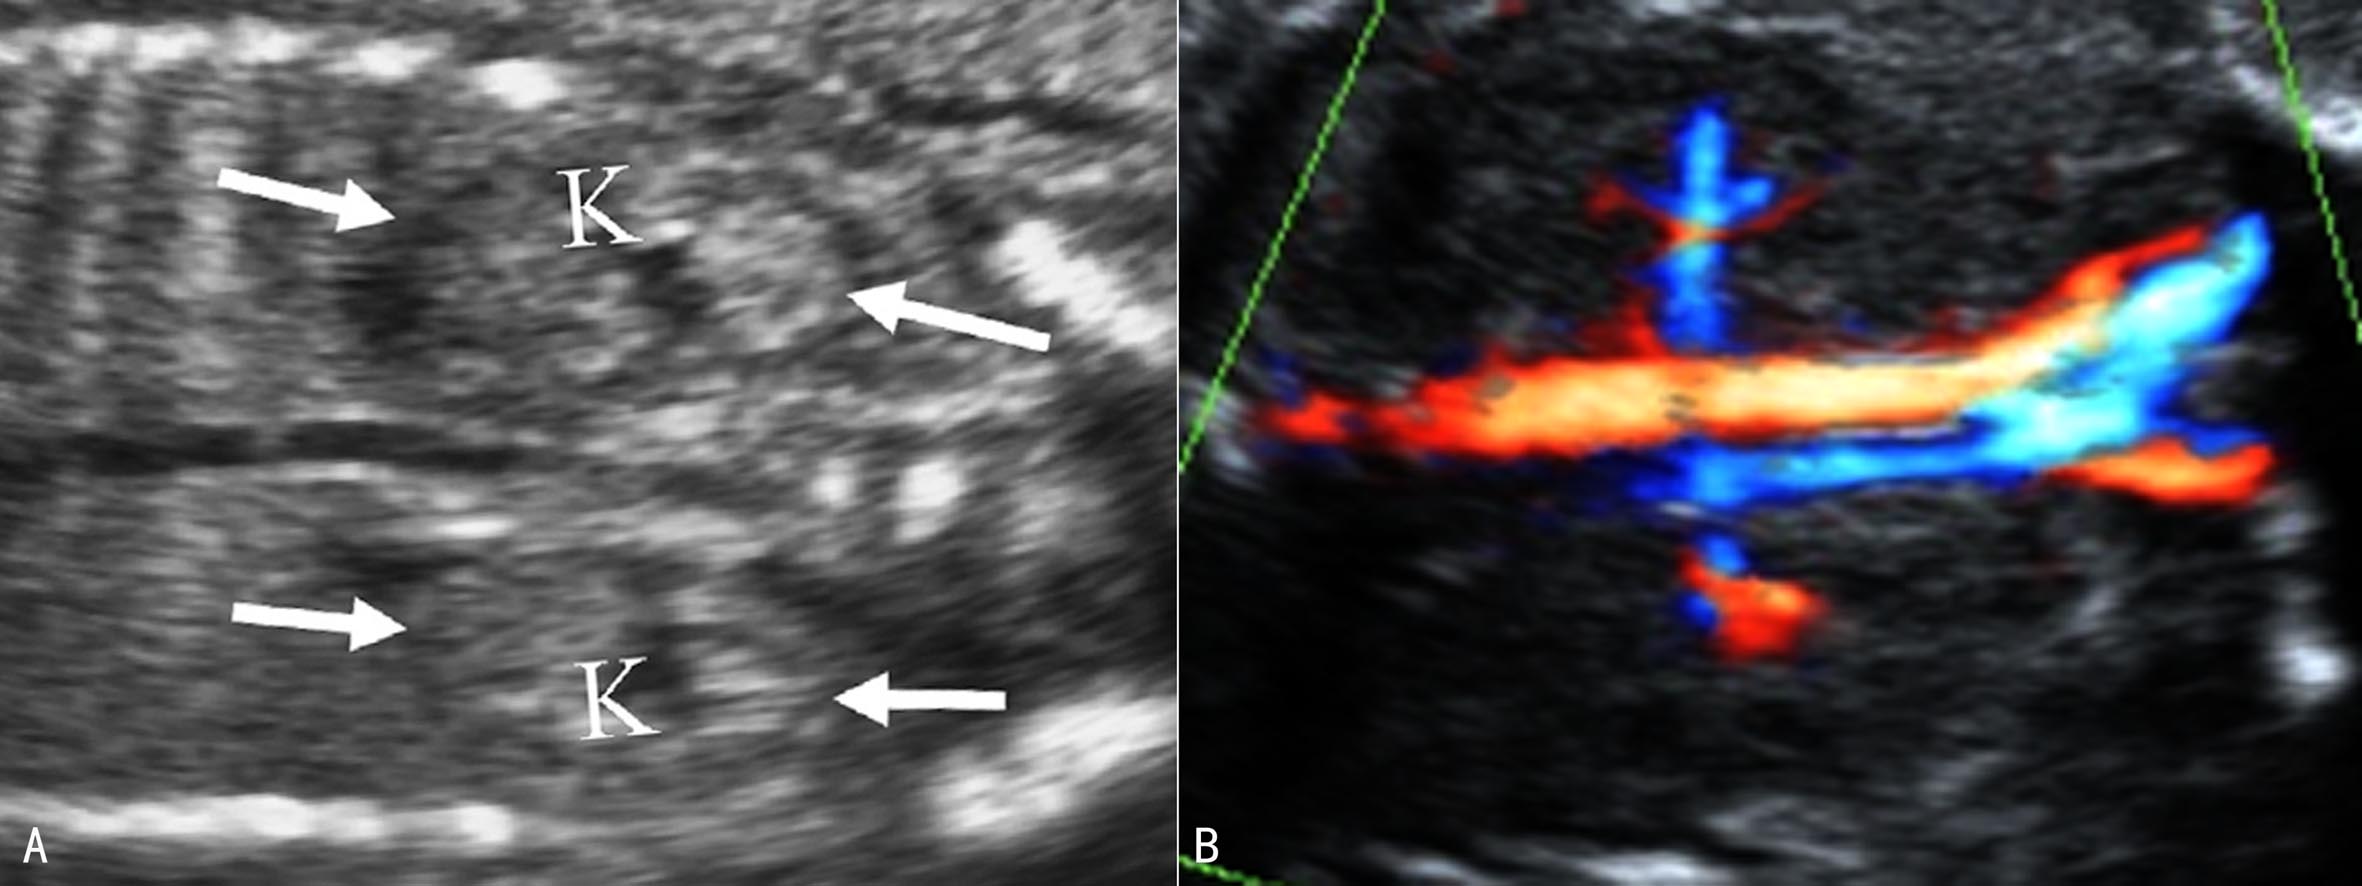

1.肾脏 孕14周时可显示出胎儿双肾,18周后可清晰显示(图5)。正常肾脏位于脊柱两旁,低于成人肾的位置,在腹部脊柱旁矢状面上呈长圆形蚕豆样,肾脏水平横切时呈圆形,右侧(RK)稍低于左侧(LK)。最初胎儿肾脏为均匀的低回声区结构。随着妊娠的进展,可见到更为详细的内部结构。等回声的肾皮质包绕在低回声的锥形髓质周围,中央强回声区为集合系统,肾盂呈无回声长条状结构,位于集合系统中央。肾外周为肾周脂肪和肾囊。当超声显像检查肾脏回声显示不清时,CDFI检查肾动脉有助于确认肾脏的存在(图6)。肾脏周长、容积、厚度和长度均与孕龄有良好的相关性,正常肾脏长度相当于4~5个椎体的高度;在整个妊娠期肾周长/腹围保持在比较恒定的0.27~0.30之间。

图5胎儿双肾纵切面声像图